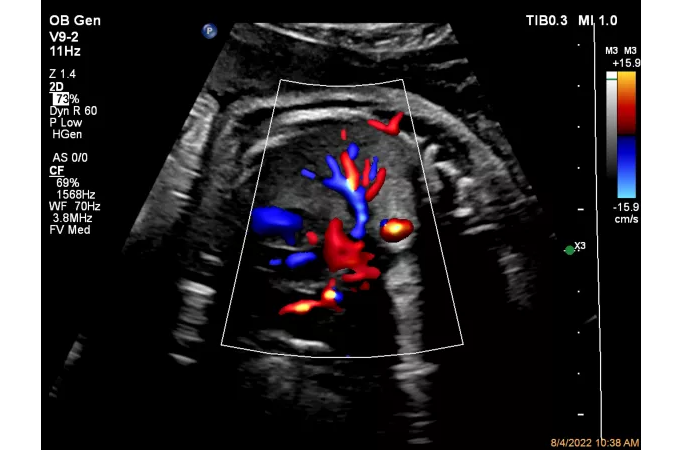

MicroFlow Imaging – мелкие сосуды в высоком разрешении

Специальная технология позволяет четко отображать на экране и снимках участки тканей с медленным или слабым кровотоком. Это очень ценно при исследованиях сосудов.

Благодаря использованию технологии специалисты получают:

- улучшенную визуализацию просветов;

- высокое разрешение в 2D и отличное качество получаемого изображения;

- минимальное количество артефактов при исследовании некрупных сосудов.

- исследование в режиме допплер (CW и тканевой);

CPA дуги аорты плода с Flow Viewer

ЦДК сердца плода, четыре камеры, с Flow Viewer

ЦДК перфузии легких плода с Flow Viewer